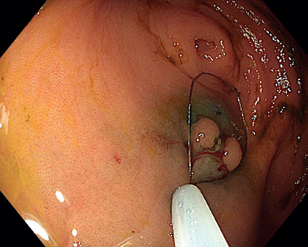

Obr. 13 Částečně disekovaná léze.Endoskopická transmurální resekce (full‑thickness resection, FTR) představuje jistou formu evropské „odpovědi” na japonskou metodu ESD. Ostatní metody (zejm. EMR a ESD) jsou limitovány na povrchové vrstvy střevní stěny, v některých případech toto ale není dostatečné. Příkladem může být výrazná fibróza pod lézí znemožňující resekci, popřípadě léze vycházející z hlubších vrstev stěny. FTR umožňuje provést resekci celé šíře střevní stěny, a to bez vytvoření volné perforace. Původní nástroje byly velmi objemné, a tedy značně komplikovaly manévrovací schopnost endoskopu, toto se změnilo s představením OTSC klipů (over‑the‑scope‑clip). S jejich použitím bylo vyvinuto zařízení na FTR (FTRD – FTR device). Jedná se o jednokrokový resekční přístroj kombinující modifikovaný OTSC klip nasazený na průhledný nástavec s předinstalovanou kličkou.

Samotná FTR začíná označením léze koagulačními body, následně se nasadí FTRD a přístroj se znovu zavede do místa léze. Ta je vtažena do nástavce s celou šířkou stěny a poté je naložen klip, který takto komprimuje duplikaturu střevní stěny vtaženou do nástavce. Po uvolnění klipu se stáhne klička a léze se odstraní za použití elektrického řezacího proudu. Takto vytvořená perforace je tedy uzavřena ještě předtím, než vznikne.

FTR se používá nejen u lézí s výraznou fibrózou, ale může být také vhodná u lézí v rizikových anatomických lokalitách, jako je v blízkosti divertiklu nebo v apendikulárním ústí. Další možné použití je v horním GIT pro resekci submukózních nádorů, jako jsou neuroendokrinní tumory (NET) a gastrointestinální stromální tumory (GIST).